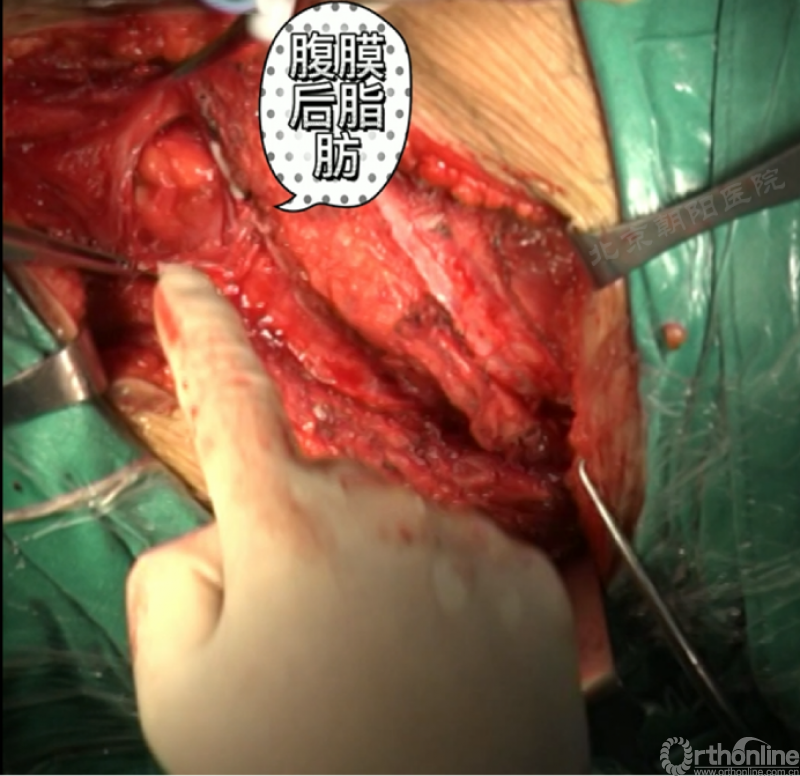

由第12肋前端软骨部位进入腹膜后间隙,可以见腹膜后脂肪。

经腹壁和横膈下方钝性分离腹膜内组织。